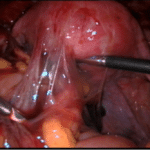

הלפרוסקופיה הינה כלי הבחירה באבחנה מדויקת של אנדומטריוזיס, מיקומה ודרגת חומרתה ומאפשרת טיפול כירורגי במחלה ללא פתיחת בטן.

ההחלטה על ביצוע לפרוסקופיה אינה פשוטה, ועליה להסתמך על גיל ותלונות המטופלת, הממצאים בבדיקה, הממצאים בהדמייה, תוכניות הפריון, טיפולי פריון קודמים ו/או ניתוחים קודמים

הלפרוסקופיה הינה כלי הבחירה באבחנה מדויקת של אנדומטריוזיס, מיקומה ודרגת חומרתה ומאפשרת טיפול כירורגי במחלה ללא פתיחת בטן. הלפרוסקופיה מאפשרת כריתת ציסטה שחלתית, הפרדת הידבקויות, כריתת נגעים לשם שיפור התלונות וטיפול באי הפריון. הלפרוסקופיה דורשת מיומנות ונסיון יחד עם עבודת צוות של מומחים בתחומים שונים לשם טיפול מיטבי